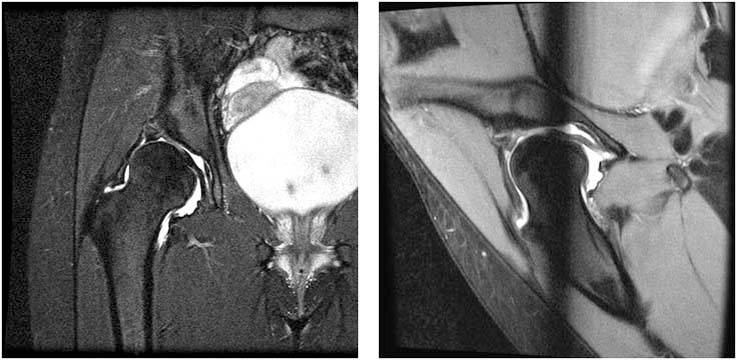

3.The images above are specialized MRI images taken from a procedure called MRI arthrography where a specialized material is injected into the hip joint and an MRI is obtained. These show the damage to the acetabular labrum as well as demonstrating the minimal coverage of the femoral head.

Figure 2: MRI of a hip with dysplasia showing much of the head uncovered by the bony roof (roof edge shown by large black arrow). The other structures of the joint such as the cartilage (large white arrows) and an enlarged labrum (small black arrows) can also be seen on the MRI image.

In younger patients, this abnormality can lead to increased pain in the hip as well as tears of the labrum. When this condition is diagnosed in adulthood and the hip is still in the non-arthritic phase, there is still a chance to intervene prior to full blown arthritis. Standard radiographs only show the damage in its final stages. Newer types of studies such as MRI (See Figure 2) can show early damage to the structures in the hip.